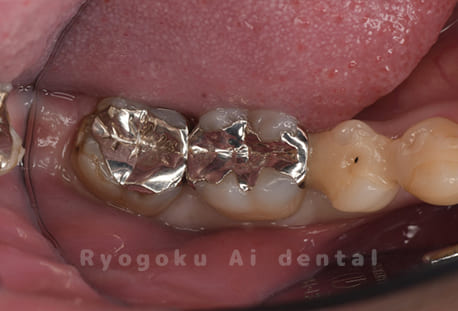

Case11

-

- 原因

- インレー2次カリエス、ならびにインレー脱離

- 治療内容

- セラミッククラウン、セラミックインレー

- 治療費用

- 123,000円×2(セラミッククラン)、77,000円(セラミックインレー)

銀歯が取れて、ご来院された患者様です。奥歯2本をセラミッククラウン、手前の小臼歯をセラミックインレーで治療を行いました。

<リスク・副作用>

過度の咬合や衝撃で割れることがあります。